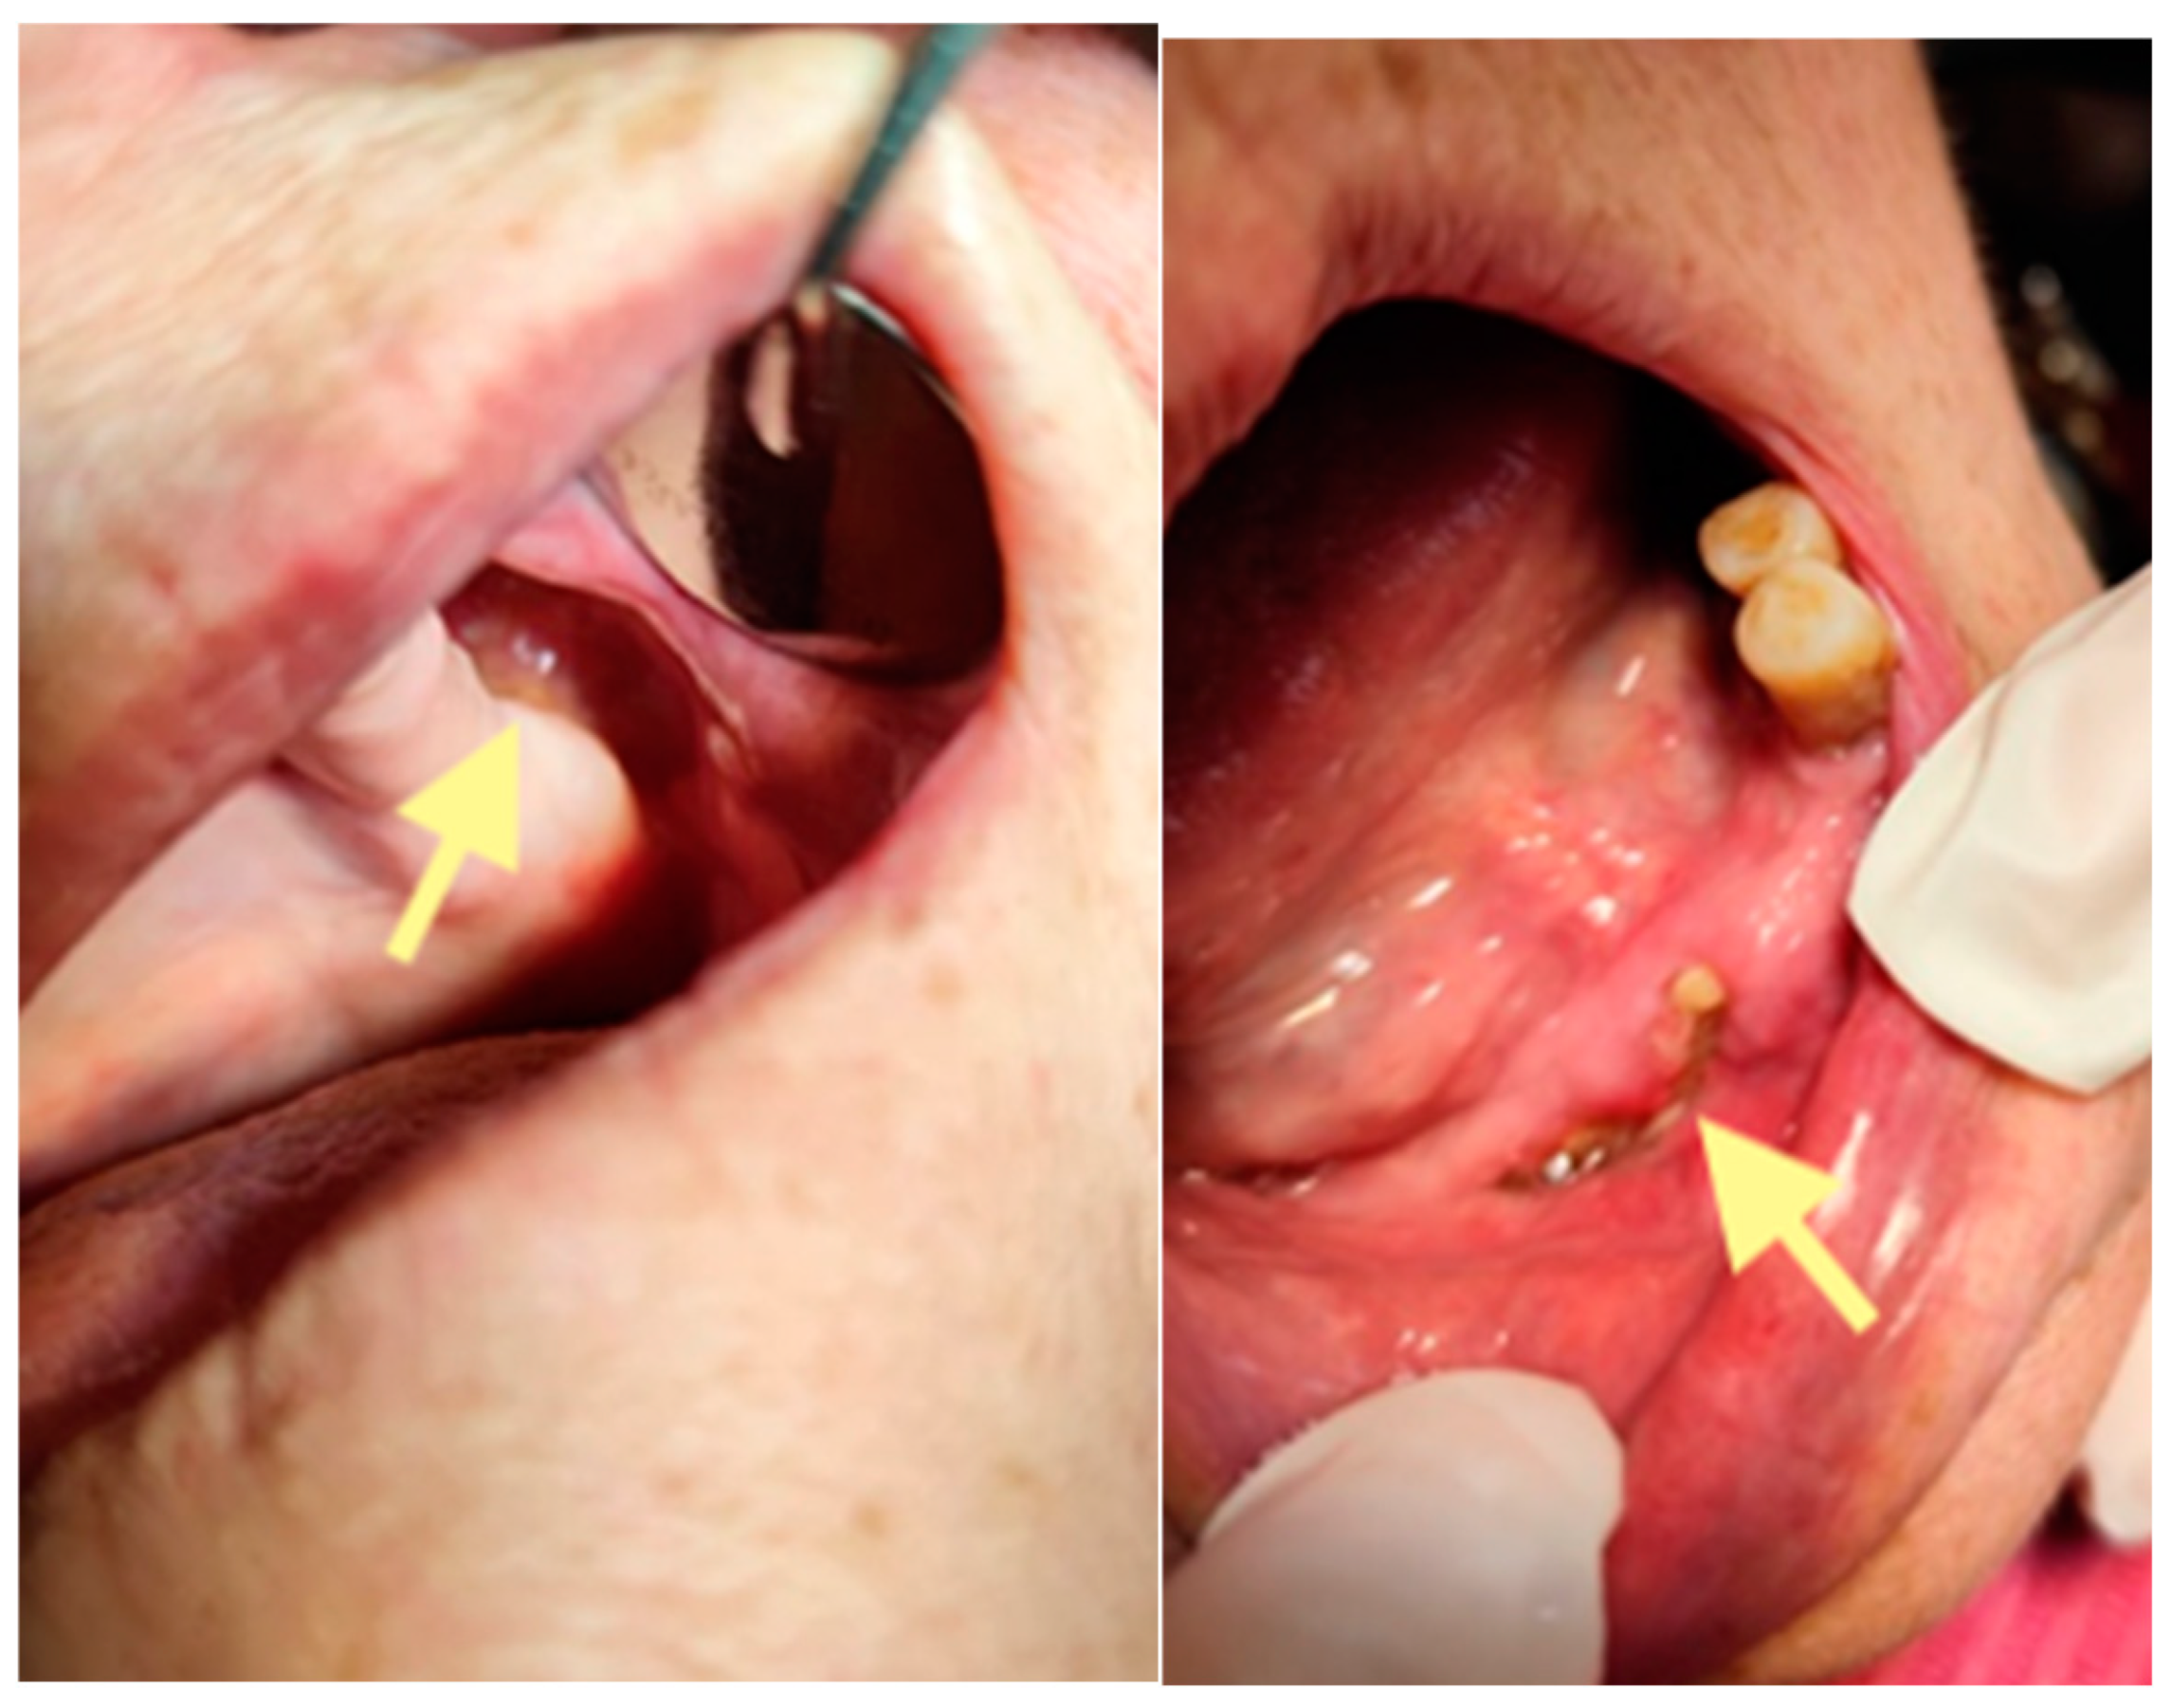

The second patient was an 82-year-old female with osteonecrosis of the mandible in the fourth quadrant, which developed after the removal of tooth 46 on November 2023 (see Figure 4). The patient had second-stage osteonecrosis of the jaw. Initially, the patient underwent a revision of the socket of the extracted tooth and was prescribed antibacterial therapy. Despite this treatment, the patient continued to complain of a non-healing wound on the lower jaw in the area of the molars with periodic purulent discharge. In addition, these complaints were supplemented by a complaint of an intraoral fistula on the lower jaw in the area of the frontal teeth. Therefore, in May 2024, the patient underwent surgery (sequestrectomy and application of A-PRF). After the operation, the patient’s condition improved, purulent discharge from the wound stopped, the pain ceased, and the postoperative wound closed completely (see Figure 4). However, after a month, dehiscence of the wound was noted. Therefore, it was decided to repeat the operation, performed on 4 April 2025, and, in addition, to expand the scope of the surgical procedure, the sequestrectomy of the lower jaw was performed not only in the region of dd45-46 but also in the central area, simultaneously applying A-PRF. As a result of the treatment, the surgical wound on the lower jaw in the area of the molars on the right healed completely, but in the area of the incisors, it closed partially (see Figure 5 and Figure 6).

Figure 5.

OPG (orthopantomogram) performed on 21.08.2024.

Figure 6.

Control visit of the patient after the second surgery, one month after the second operation performed on 28 May 2025.

However, on 29 September 2025 (last control visit), we noticed complete healing in both areas of the lower jaw. The patient could use a new partial plate for the lower jaw.